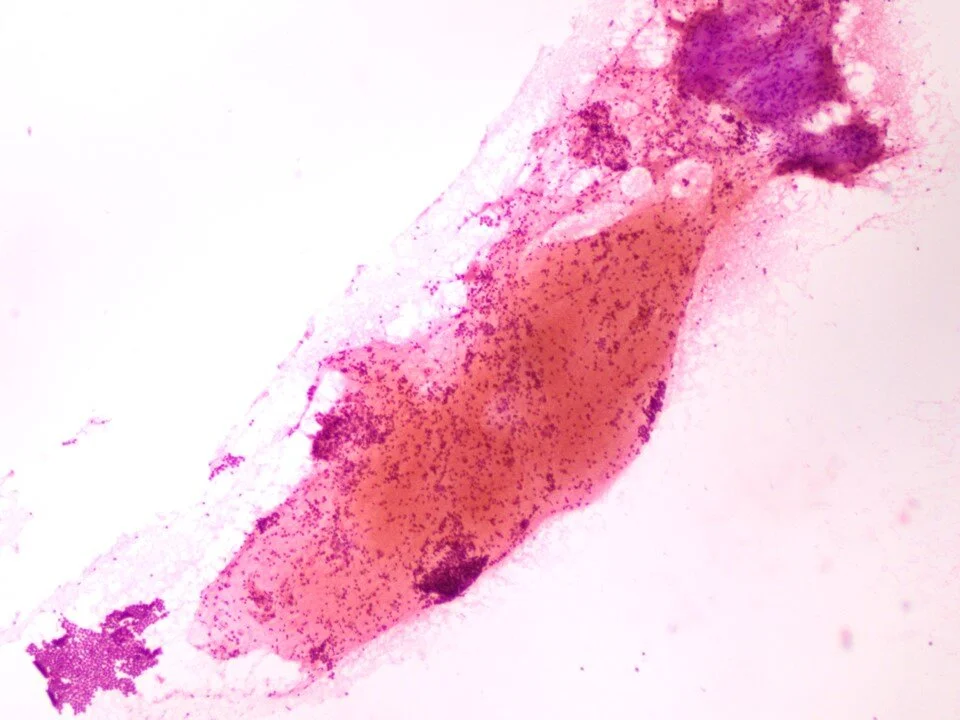

Pneumocystis jirovecii